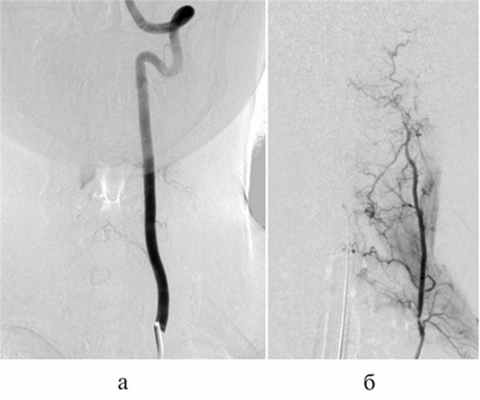

Рис. 2. Селективная спинальная ангиография.

а, б — селективная ангиография левой позвоночной артерии; определяется интрамедуллярная артериовенозная мальформация, кровоснабжаемая из корешковой артерии, с наличием интранидальных аневризм (стрелки); в — селективная ангиография щитошейного ствола слева, определяется дополнительное кровоснабжение артериовенозной мальформации из восходящей артерии шеи.

Рис. 3. Левосторонняя вертебральная ангиография, венозная фаза.

Определяется венозный дренаж артериовенозной мальформации.

На МРТ шейного отдела позвоночника на вторые сутки после операции определялось уменьшение зоны отека спинного мозга выше и ниже АВМ. Через 3 мес выполнена контрольная селективная спинальная ангиография (рис. 6, а, б) и МРТ шейного отдела позвоночника (рис. 7), по данным которых признаков функционирования АВМ не выявлено. Клинически отмечено улучшение в виде полного регресса верхнего левостороннего монопареза и чувствительных расстройств.

Рис. 6. Контрольная ангиография через 3 мес после операции.

а — селективная ангиография левой позвоночной артерии, артериовенозная мальформация не контрастируется; б — селективная ангиография левого щитошейного ствола, артериовенозная мальформация не контрастируется.